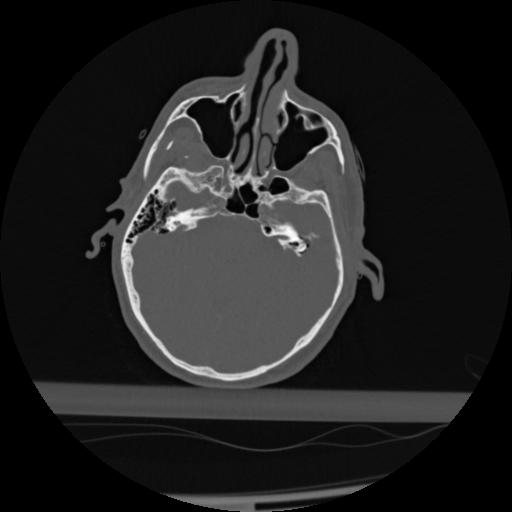

22 ANGIO,CE,Vol,0.5,ANGIO,,